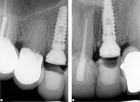

Saad A et al Nonsurgical management of interdental papilla associated with multiple maxillary implants. Journal Prosth, 2005; 93: 212-215. The patient had received two adjacent implants in the #22 and #23 position. Predictably the final result was an esthetic failure. Maximum tissue height between two implants is only 3.5 mm. Result was predictably an esthetic failure.

The patient had received two adjacent implants in the #22 and #23 position. Predictably the final result was an esthetic failure. Why? Firstly, interdental bone requires blood supply and adjacent implants compromise blood supply.13 Secondly, the BW; that minimum amount of soft tissue (vertical and horizontal) whose primary function is to insulate the underlying bone both, from the outside environment is sub-crestal around implants, reducing the ultimate height of the papilla. Bone will be lost in both dimensions until this criterion is met.11,12,13,15,16 The author recognized this and buried the #22 implant to create a pontic instead and allow soft tissue to granulate into the site as a means of BW enhancement (increased insulation) around the remaining exposed implant.

The final result was a marked improvement over the initial result.